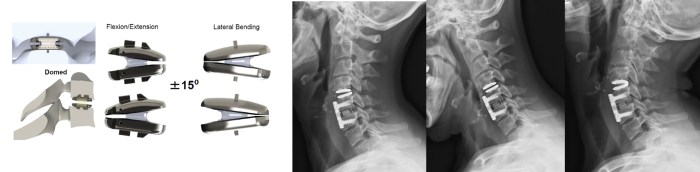

An arthrodesis of several cervical levels could limit the function of the cervical spine (flexion, extension, lateral flexion and rotations).

The cervical disc prosthesis maintains or restores the mobility of the adjacent cervical levels and therefore limits or avoids these problems.

The limited cervical disc herniation which did not improve with the conservative treatment and with a limited cervical arthritis, is the ideal indication for the cervical prosthesis.

A prosthesis could be inserted in a more severe uncodiscarthritis if during the procedure a circumferential resection of the arthritic tissue is possible.